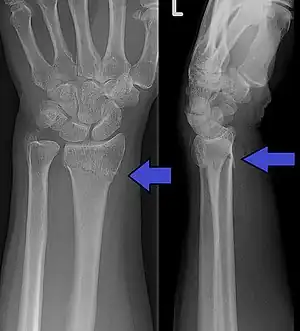

Diagnosis may be evident clinically when the distal radius is deformed, but should be confirmed by X-ray. The differential diagnosis includes scaphoid fractures and wrist dislocations, which can also co-exist with a distal radius fracture. Occasionally, fractures may not be seen on X-rays immediately after the injury. Delayed X-rays, X-ray computed tomography (CT scan), or Magnetic resonance imaging (MRI) can confirm the diagnosis.

X-ray of the affected wrist is required if a fracture is suspected. Posteroanterior, lateral, and oblique views can be used together to describe the fracture.[4] X-ray of the uninjured wrist should also be taken to determine if any normal anatomic variations exist before surgery.[4]